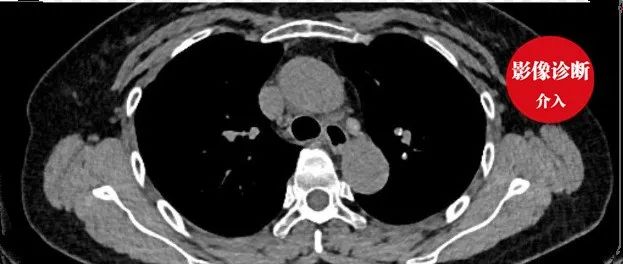

肺动脉 CTA 不会看?这篇教你轻松诊断肺栓塞!

肺栓塞(PE)各位都不会陌生,它的栓子可以是血栓、脂肪栓塞、羊水、肿瘤和空气等,其中由血栓引起的肺栓塞称之为肺血栓栓塞症 PTE 。因其不典型的症状和较高的致死率(诊断不明确的患者死亡率约 30%),肺栓塞一直是临床工作当中的沉默杀手。尽管患者在 48 小时之内接受干预可以获得较好的生存率,但如何早期有效地揪出这个「杀手」始终是临床医生面对的重中之重。CT 肺动脉造影(CTPA)简便、无创,且敏感性和特异性都很高,是诊断肺栓塞的首选检查。本文拟通过分析 CTPA 的图像表现,帮助大家更好地诊断肺栓塞。...